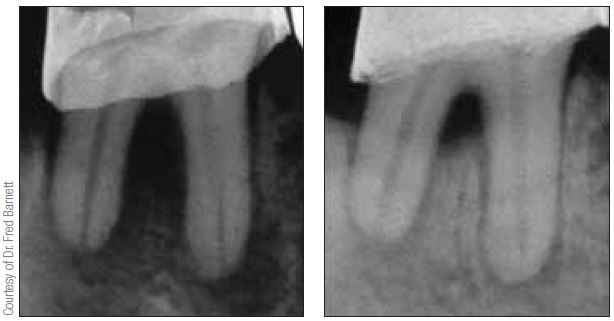

UltraCal XS de Ultradent Products, Inc. es una formulación acuosa y radiopaca de una pasta de hidróxido de calcio no fraguable, con un pH de 12,5. Esta pasta premezclada se dispensa o “inyecta” desde una jeringa a través de la punta de aplicación NaviTip 29ga directamente dentro del conducto. Además de generar un resultado más confiable, especialmente en los dientes posteriores, la colocación de hidróxido de calcio con una NaviTip 29ga elimina la posibilidad de separación de un instrumento en espiral durante el procedimiento. Cuando se produce la separación de un instrumento dentro del conducto, es problemático para el odontólogo tratante y es posible que requiera de un especialista. UltraCal XS permite al operador dispensar la cantidad correcta de hidróxido de calcio a la longitud de trabajo, evitando que el material sea forzado inadvertidamente más allá del foramen apical hacia los tejidos perirradiculares, especialmente si existe una lesión crónica o extensa.